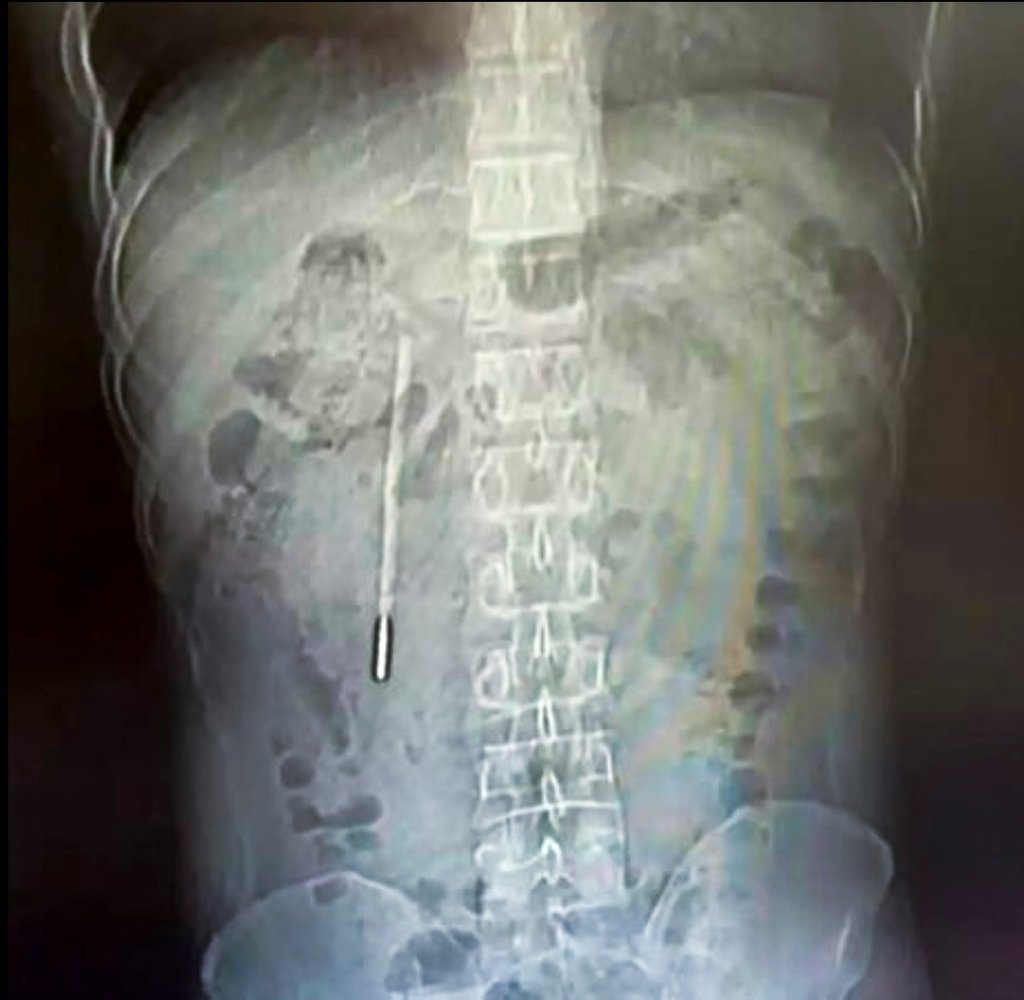

Theo kết quả từ các biện pháp chẩn đoán hình ảnh và chụp chiếu, các bác sĩ chuyên khoa đã phát hiện một dị vật nằm sâu bên trong tá tràng của bệnh nhân. Căn cứ vào hình dáng và đặc điểm trên phim chụp, đội ngũ y tế đã đặt ra nghi ngờ rất lớn rằng vật thể lạ này chính là một chiếc nhiệt kế thủy ngân.

Tình trạng lúc bấy giờ được đánh giá là vô cùng nguy hiểm. Phần đầu nhọn của chiếc nhiệt kế đang trong trạng thái ép trực tiếp vào lớp thành ruột của bệnh nhân. Vị trí và tư thế này đặt ra một nguy cơ cực kỳ cao về việc gây thủng ruột và dẫn đến tình trạng chảy máu trong nghiêm trọng, đe dọa trực tiếp đến tính mạng của người bệnh nếu không được can thiệp kịp thời.